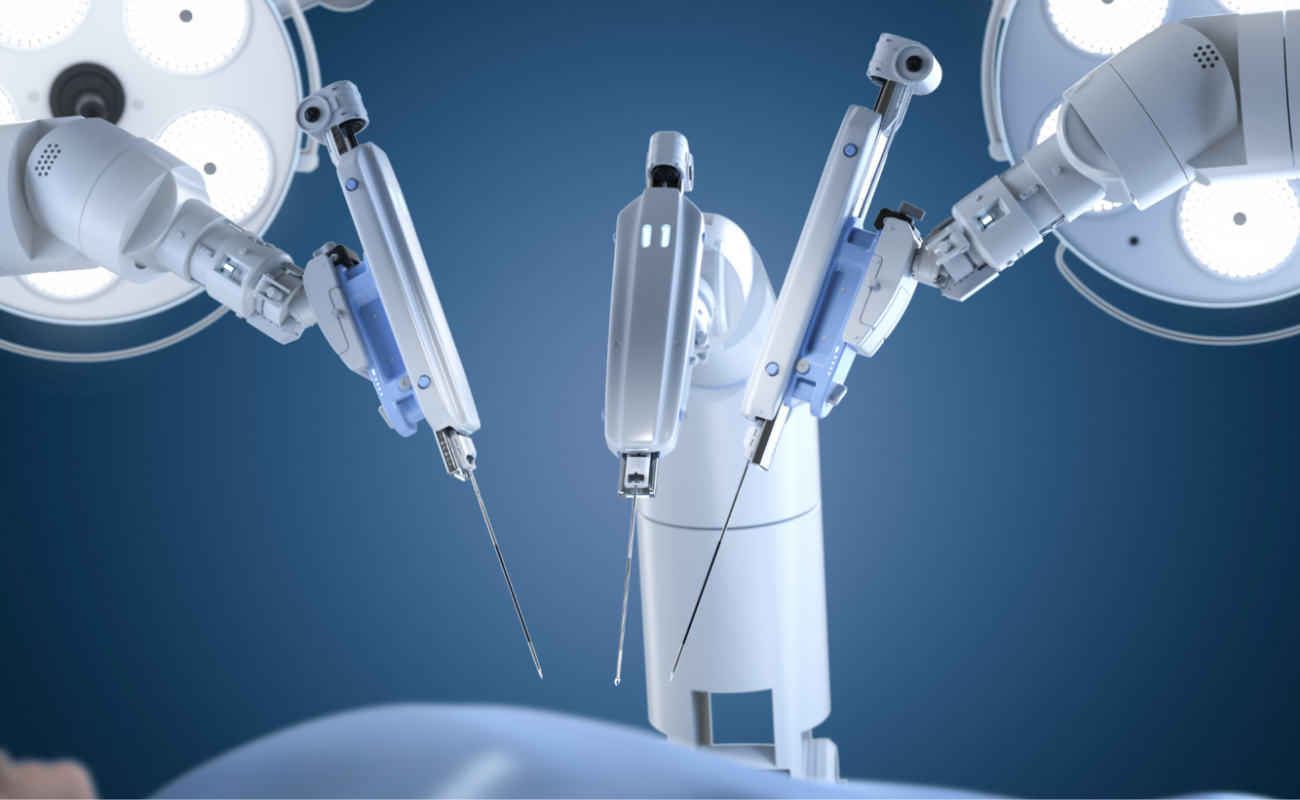

With state-of-the-art robotic joint replacement surgery offering greater accuracy, smaller incisions, and faster recovery times.

The Benefits of Robotic Knee Replacement Surgery

In recent years, medical technology advancements have brought about a revolution in the field of orthopedic surgery, particularly in the realm of knee replacements.

The Impact of Robotics on Knee Replacement: Revolutionizing Orthopedic Surgery

In recent years, orthopedic surgery has undergone a revolutionary transformation through the integration of robotics in knee replacement procedures.

Knee Replacement Surgery: A Comparison of Traditional and Robotic Techniques

When it comes to addressing debilitating knee pain and restoring mobility, knee replacement surgery has been a transformative solution for many individuals.

Robotic Surgery: The Future of Healthcare in Chennai

Robotic surgery is revolutionizing healthcare, particularly in Chennai, where advanced medical techniques are becoming increasingly accessible

Chennai Apollo hospital performs 370 robot-assisted orthopedic procedures in 10 months

A robotic knee replacement is just like a traditional knee replacement. The surgeon removes damaged tissue and replaces it with an artificial joint.

Robotic Surgery in Chennai: A Guide for Patients and Caregivers

Robotic surgery is transforming modern healthcare, offering precision, minimally invasive techniques, and faster recovery for patients. As one of the most significant advancements in surgical technology,

What Are the Benefits of Robotic Surgery and Why Do People Choose It?

A surgeon’s hands have been augmented by a machine capable of millimeter-perfect precision. Robotic surgery, a groundbreaking medical innovation that is redefining surgical care around the world, including India. With benefits ranging from minimal

Modern Technology Makes Robotic Surgery Safer Than Ever

In the world of surgery, one technology that has made waves since its introduction is robotic surgery. It has swiftly moved from novelty to necessity in the medical world. Robotic surgery has changed every surgeon’s